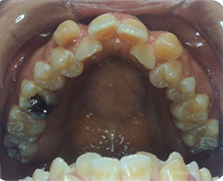

骨格性の問題が大きい歯並び(上顎) 骨格性の問題が大きい歯並び(下顎)

骨格性の問題が大きいので、当クリニックで矯正治療する場合は、 外科矯正治療となります。費用は顎変形症の適応となりますので、保険適応となります。装置は歯の表側よりブラケットという装置を装着します。期間は3年前後は必要かと思います。上顎は配列する為に両側で1本づつの抜歯が必要となります。下顎の左側 は親知らずの抜歯が必要です。右側は小臼歯が埋伏してるとの事なので、牽引できる

場合は保存しますが、状況により抜歯が必要となります。